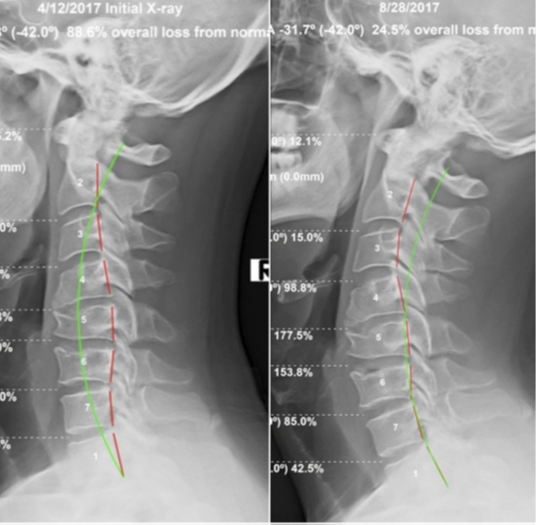

Figure 3. Before Treatment: Cervical Kyphosis. After Treatment— Restoration of Cervical Curve to the amount possible due to structural deformity of the C4-C6 vertebral segments.

Post-treatment radiographic measurements demonstrated structural changes rarely documented in the peer-reviewed literature without surgical intervention. Global cervical lordosis improved from –4.8° (near-zero) to –31.7° — a gain of 27 degrees representing a 560% improvement. Localised C4–C6 kyphosis reduced by 5°. Anterior head translation decreased from 7.3 mm to 3.8 mm, a 48% normalization.

Clinical disability scores mirrored the radiographic gains. The Neck Disability Index dropped from 30% (moderate disability) to 16% (mild disability) — a clinically meaningful reduction exceeding the established minimal detectable change threshold. Grip strength increased by 4 lbs per hand bilaterally, reflecting improved cervical nerve root function.